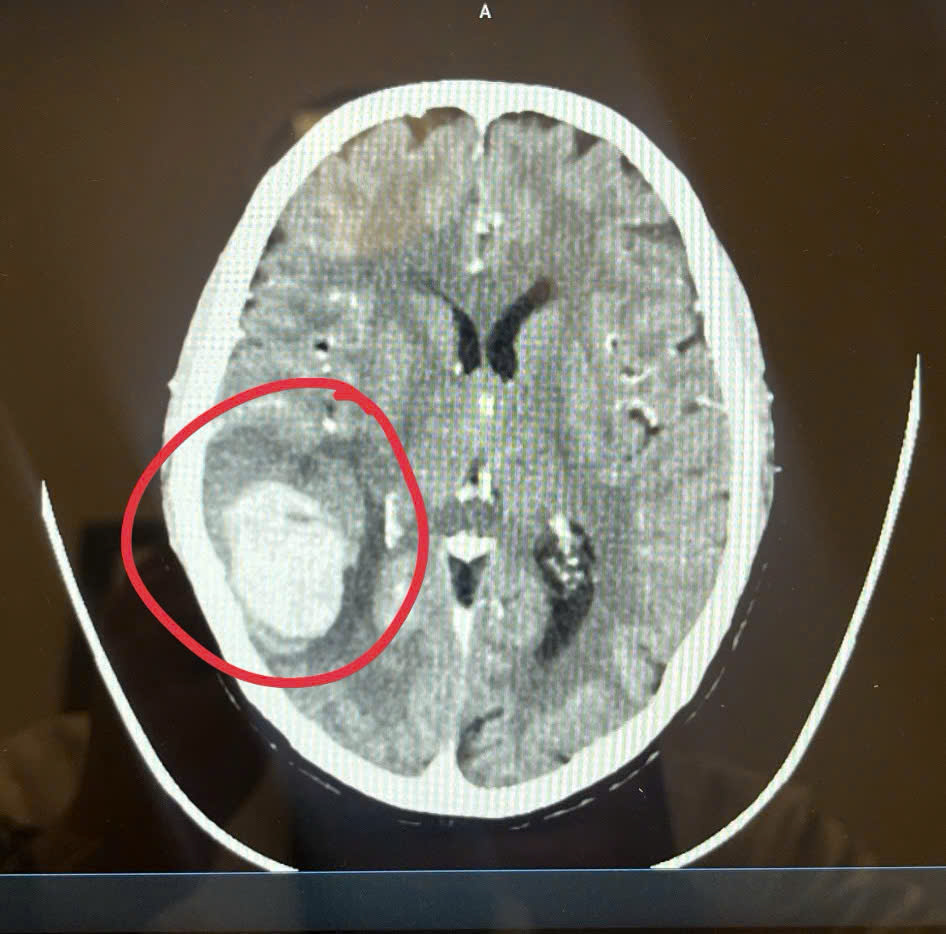

แพทย์ตรวจพบเลือดออกในสมองร่วมกับความดันโลหิตสูง ทำให้การรักษาเร่งด่วนเป็นกุญแจสำคัญ เธอเข้าถึงโรงพยาบาลเร็ว จึงไม่เกิดความพิการรุนแรง เหตุการณ์นี้ตอกย้ำว่า “รู้ไว ไปไว รอดไว” คือหลักจำง่ายที่ทุกคนควรยึด

แพทย์ตรวจพบว่าผู้ป่วยมีอาการใบหน้าเบี้ยวจาก เลือดออกในสมอง และความดันโลหิตสูงถึง 200 มม.ปรอท ซึ่งเป็นสาเหตุหลักของภาวะหลอดเลือดสมองแตก โชคดีที่เธอมาถึงโรงพยาบาลเร็ว ทำให้แพทย์สามารถรักษาได้ทันก่อนเกิดภาวะสมองเสียหายถาวร